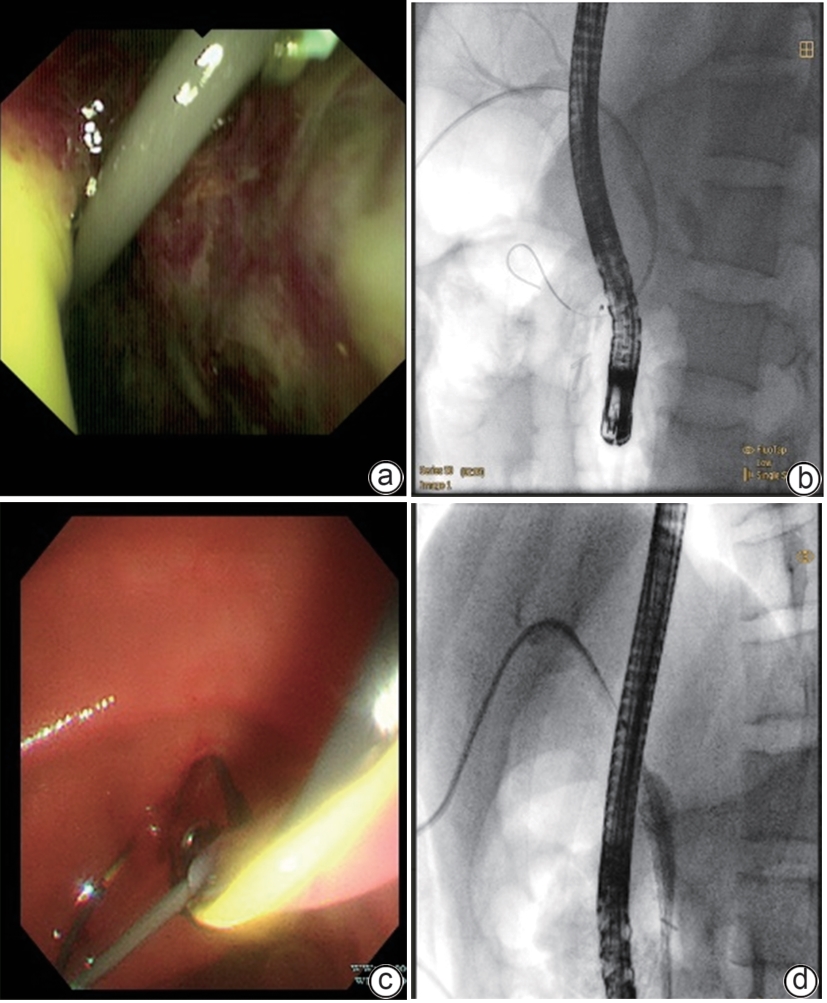

Successful treatment of biliary fistula after Beger surgery by oral choledochoscopy-assisted percutaneous-endoscopic rendezvous technique: A case report

Yuxin WANG, Weigang GU, Zheng JIN, Xiaofeng ZHANG

2025, 41(2): 333-336. DOI: 10.12449/JCH250220

Abstract(927) HTML (261) PDF (4794KB)(52)

Abstract:

Duodenum-preserving pancreatic head resection, also known as Beger surgery, has a high incidence rate of bile duct injury after surgery, while the treatment modality for bile duct injury depends on the severity of the injury, and endoscopic therapy is often challenging in case of severe bile duct injury. Recently a patient with biliary fistula after Beger surgery was admitted to Affiliated Hangzhou First People’s Hospital, Westlake University, and successful diagnosis and treatment were achieved through oral choledochoscopy-assisted percutaneous-endoscopic rendezvous technique.